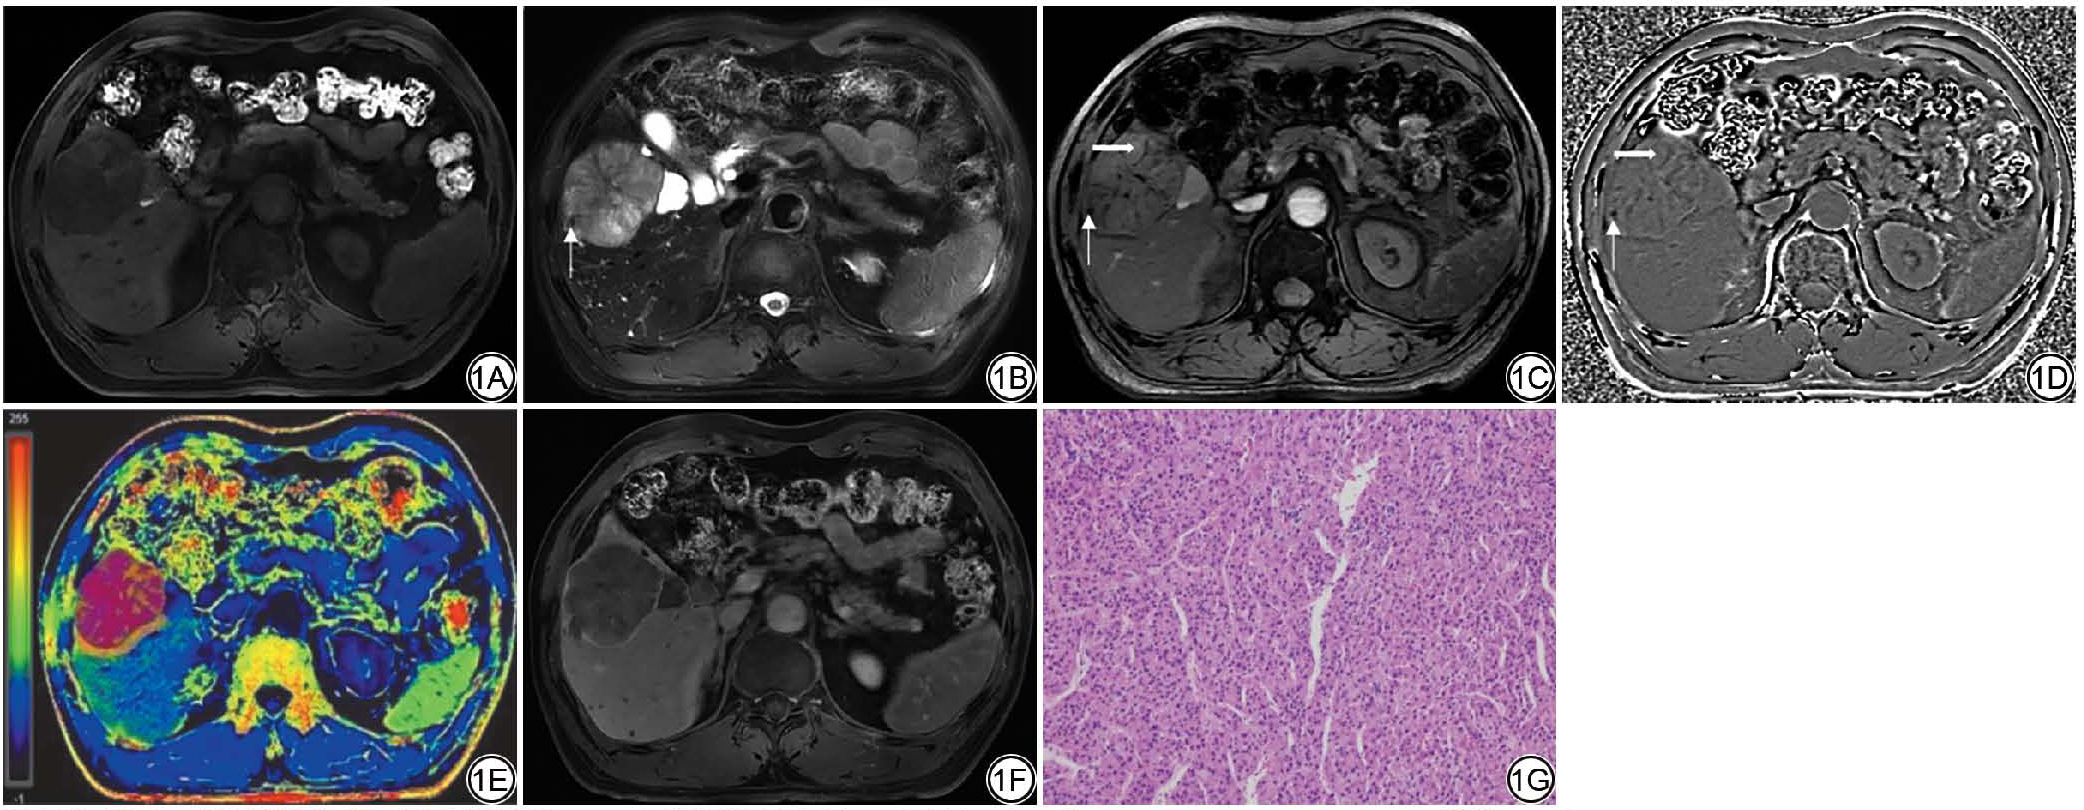

与MVI阴性组相比,MVI阳性组病灶ITSS分级更高,差异具有统计学意义(图1图2);两组之间病灶、瘤周R2*值差异无统计学意义,MVI阳性组△R2*高于MVI阴性组,差异具有统计学意义(表4)。

图1  男,58岁,病理证实为中分化肝细胞癌(HCC),微血管侵犯(MVI)分级M1级。1A~1B:分别为T1WI、T2WI图像,病灶信号均匀,T2WI病灶内可见点状出血低信号(细箭);1C~1D:磁敏感加权成像(SWI)幅值图病灶内可见低信号点状出血(细箭)及条状血管结构(粗箭),相位图呈低信号,肿瘤内磁敏感信号强度(ITSS)分级2级;1E:R2*伪彩图(蓝色至红色表示R2*值逐渐升高):病灶及瘤周5 mm区域感兴趣区(ROI)划定,△R2*=0.337;1F:Gd-EOB-DTPA增强MRI病灶可见不完整包膜结构;1G:组织病理学(HE ×200)证实为中分化HCC,MVI分级M1级。

Fig. 1  A 58-year-old male patient with pathologically confirmed moderately differentiated hepatocellular carcinoma (HCC), with microvascular invasion (MVI) grade M1. 1A-1B: T1WI and T2WI images, respectively, showing blood products within the lesion (arrow); 1C-1D: susceptibility weighted imaging (SWI) magnitude image reveal hypointense punctate hemorrhages (thin arrow) and linear vascular structures (thick arrow) within the lesion, the phase image exhibits low signal intensity, with an intratumoral susceptibility signal intensity (ITSS) grade of 2; 1E: R2* pseudo color image (the transition from blue to red indicates a gradual increase in R2* values): region of interest (ROI) delineation of lesion and 5 mm surrounding area, △R2* = 0.337; 1F: Gd-EOB-DTPA-enhanced MR shows an incomplete enhancing capsule; 1G: Histopathology (HE × 200) confirms moderately differentiated HCC with MVI grade M1.